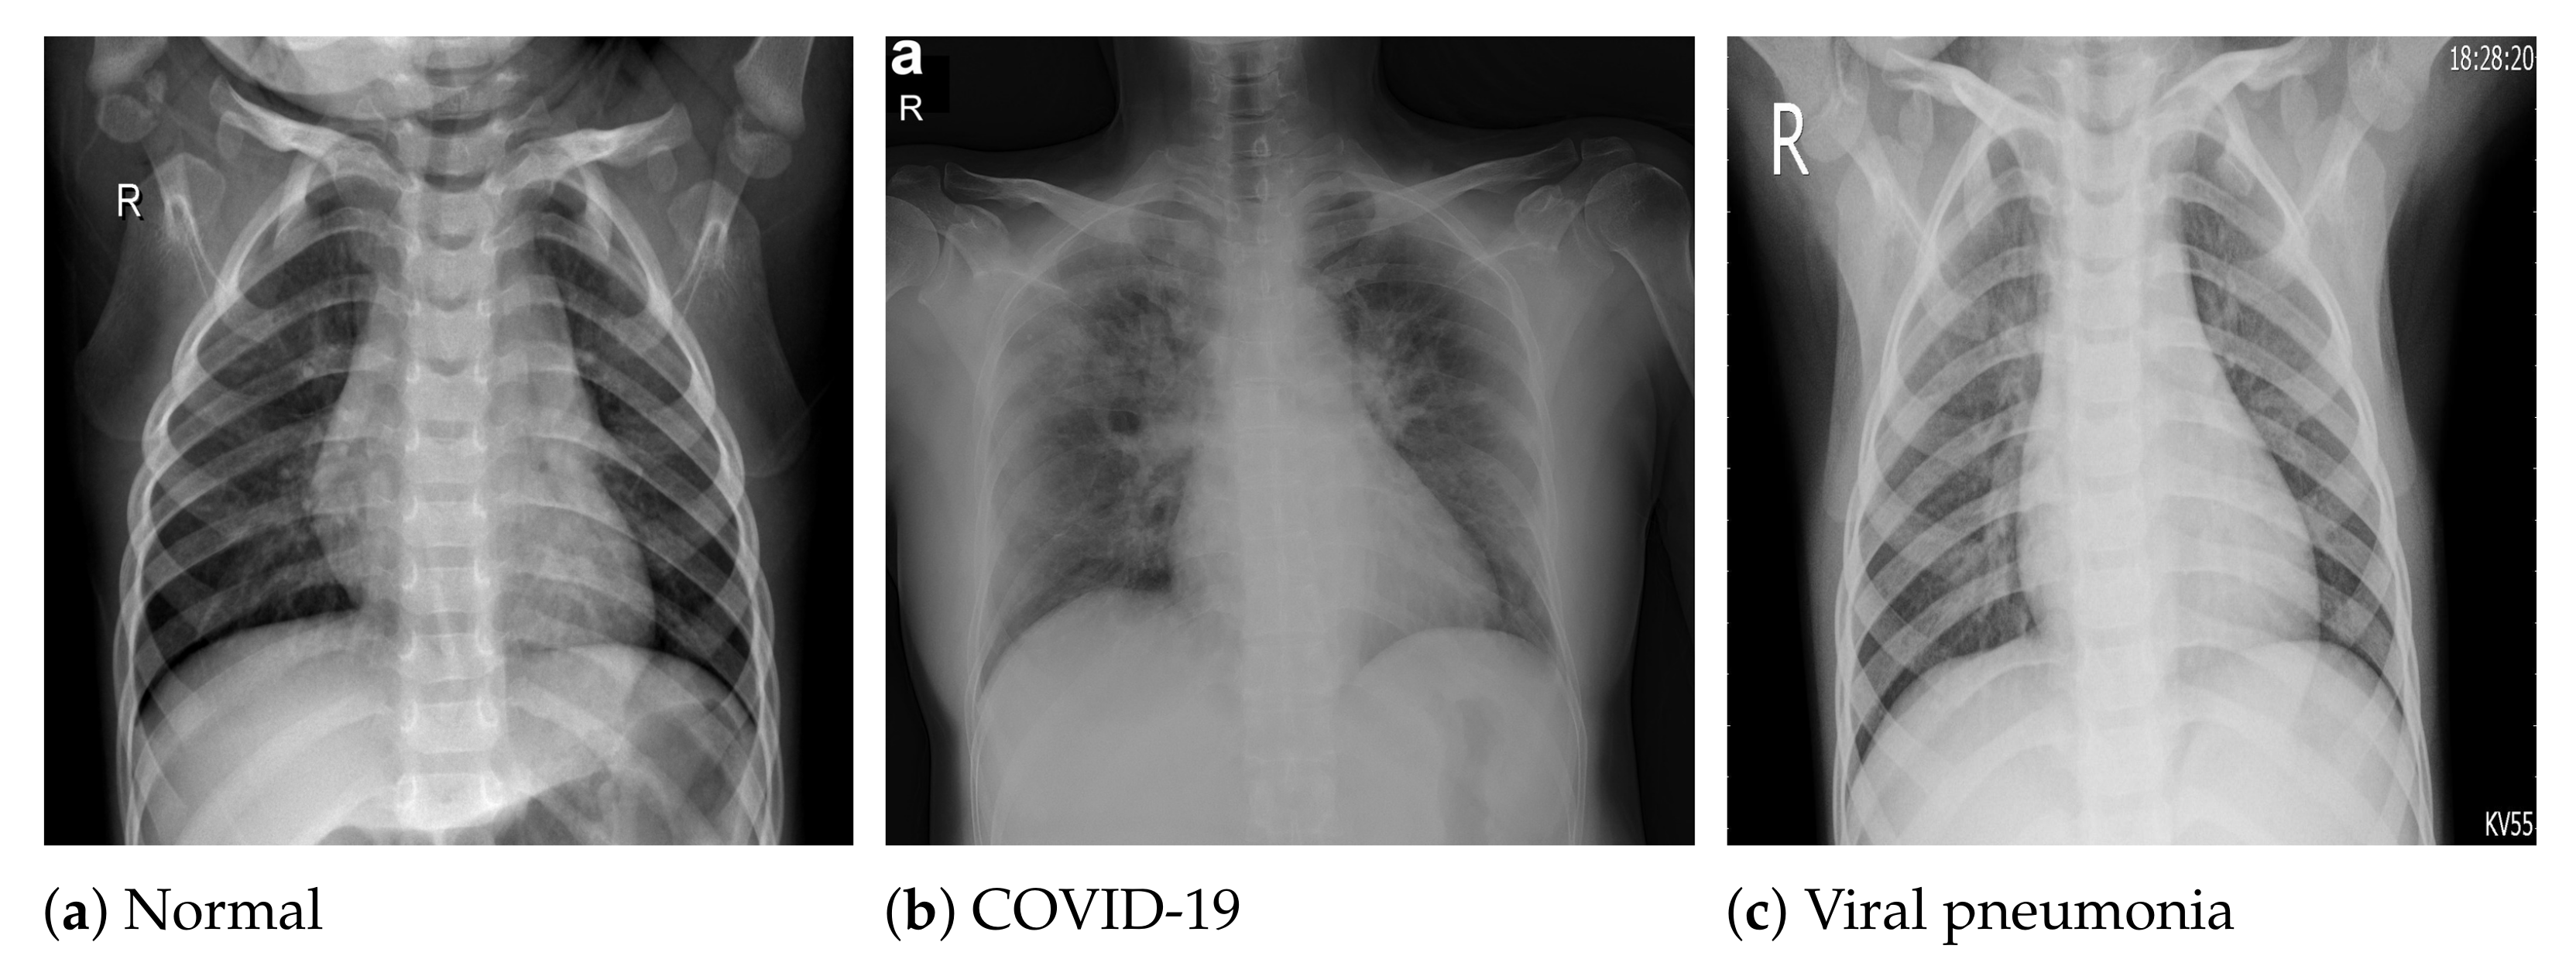

The COVID-19 radiography database [54] was selected for this work. This database was compiled by a team of researchers from the University of Doha in Qatar and the University of Dhaka in Bangladesh, who collaborated with medical doctors from Pakistan and Malaysia to create a database of chest X-ray images for COVID-19-positive cases along with normal and viral pneumonia images. The database consists of 2905 chest X-ray images, including 219 COVID-19-positive images, 1341 normal images and 1345 viral pneumonia images. The images in the COVID-19 radiography database were collected from various sources, including the Italian Society of Medical and Interventional Radiology (SIRM) COVID-19 database [64], Cohen et al.’s COVID-19 image data collection [65], the ChestX-ray8 database [46], the Kermany et al. [66] pneumonia chest X-ray images dataset, as well as some online repositories [54], where physicians and researchers have uploaded COVID-19-related chest X-ray images. All the images are stored in Portable Network Graphics (PNG) file format (24 bit RGB), with a resolution of pixels. Figure 1 depicts sample images from the database for COVID-19, normal and viral pneumonia chest X-ray images.

Figure 1.

Sample X-ray images from the used dataset.